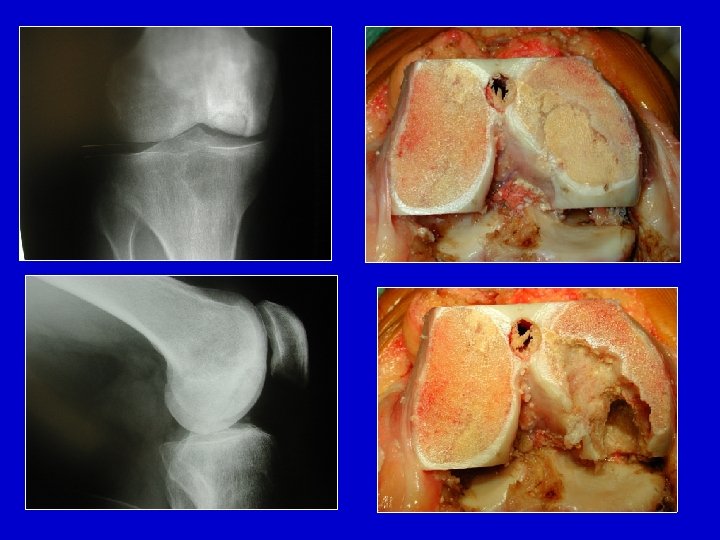

Osteocondrite aperta , il frammento è ancora in posizione

La nicchia , spesso, é coperta da tessuto fibroso

Aspetto dei corpi estranei osteocartilaginei